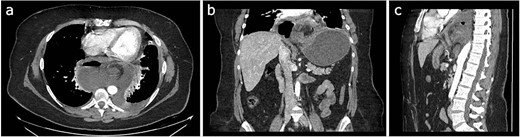

Abdominal ultrasonography (USG) showed cholelithiasis without cholecystitis or other anomalies. However, a contrast-enhanced CT exhibited distension of the gastric chamber, with inversion of the positions of the pylorus and the esophagogastric junction, and free intraabdominal air/features suggesting perforation (Fig. 1). Laboratory testing revealed an elevated white blood cell count of 22 K/uL and a protein C-reactive of 257. Electrolytes were within normal limits. Amylase and lipase were normal.

Different sections of the CT study demonstrate the mediastinal position of the gastritis volvulus. (a) Axial CT section of the abdomen showing the stomach body twisted inside the mediastinum. A hydro air level is seen at the right of the stomach body. (b) The coronal CT section of the thorax and the abdomen shows the twisting and dilatation of the reminiscent abdominal portion of the stomach. (c) Sagittal CT section of the thorax and the abdomen showing the posterior mediastinal position of the twisted stomach body.